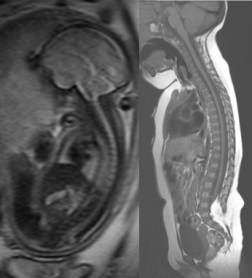

- le diagnostic est rarement fait en anténatal car il n’y a le plus souvent pas de kyste. à un stade précoce de la grossesse. la lésion peut prendre l’aspect d’un kyste à paroi épaisse, cette paroi va progressivement se charger de graisse à mesure que le kyste va régresser. de plus, les structures ne sont pas encore habitées par la graisse jaune, d’où un aspect IRM surprenant (avec la forme d’un lipome mais pas la couleur cf ci-contre).